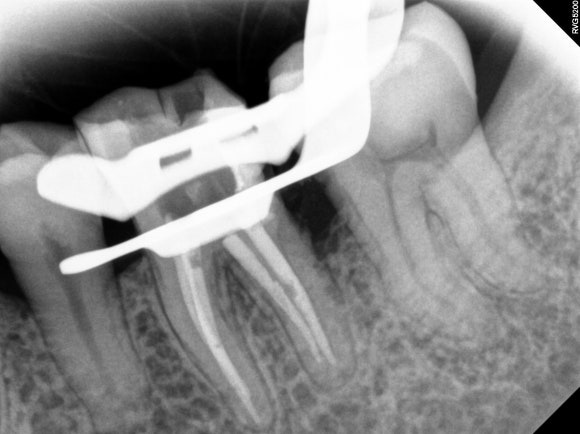

이번 증례는 어금니의 해부학적 구조상 근관이 복잡하게 분지되어 있어 각별히 세심한 처치가 필요했습니다.

신경치료를 완료한 사진